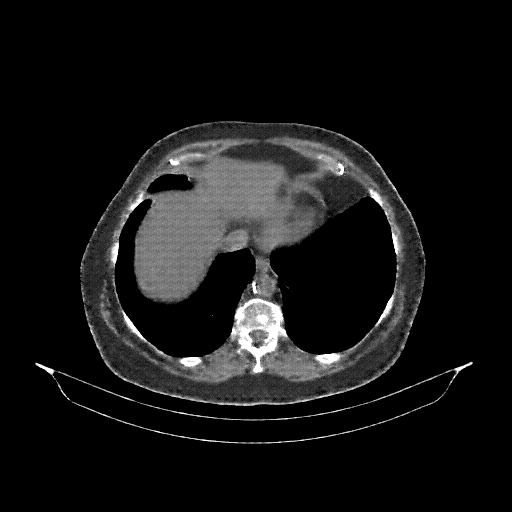

Original VENOUS CT scan

Full window (WL 1023.5, WW 4095 β†’ Low βˆ’1024, High +3071)

Lung window (WL -600, WW 1500 β†’ Low βˆ’1350, High +150)

Mediastinum window (WL 40, WW 400 β†’ Low βˆ’160, High +240)